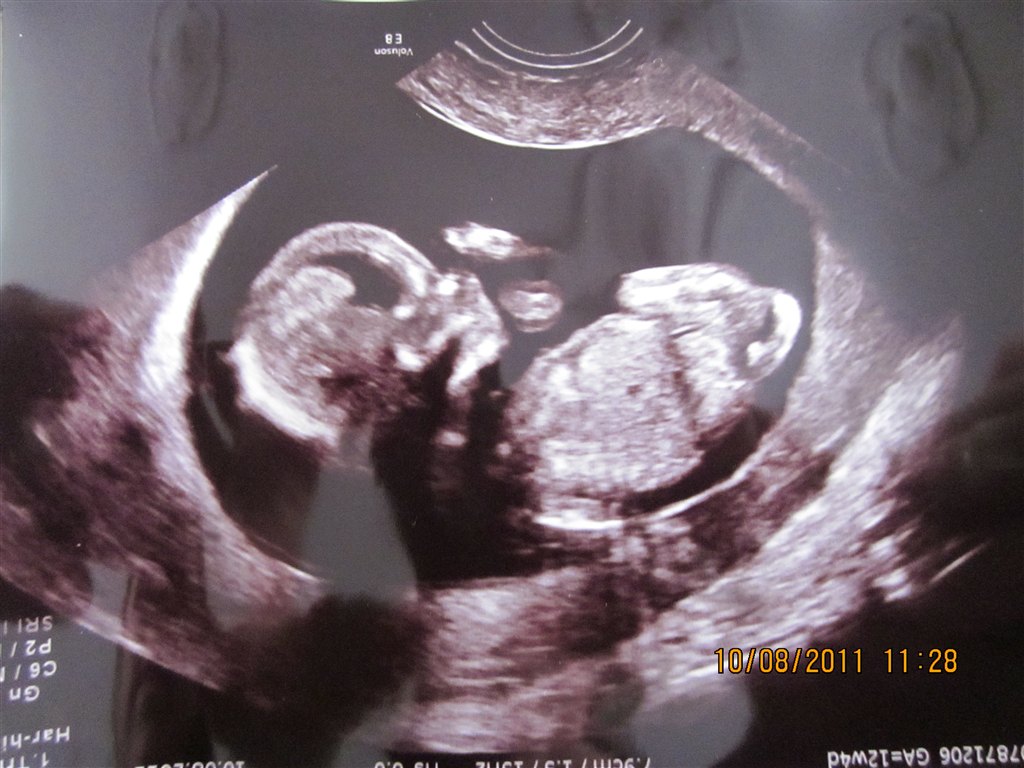

Var det ikke bare sjovt at se den lille derinde?